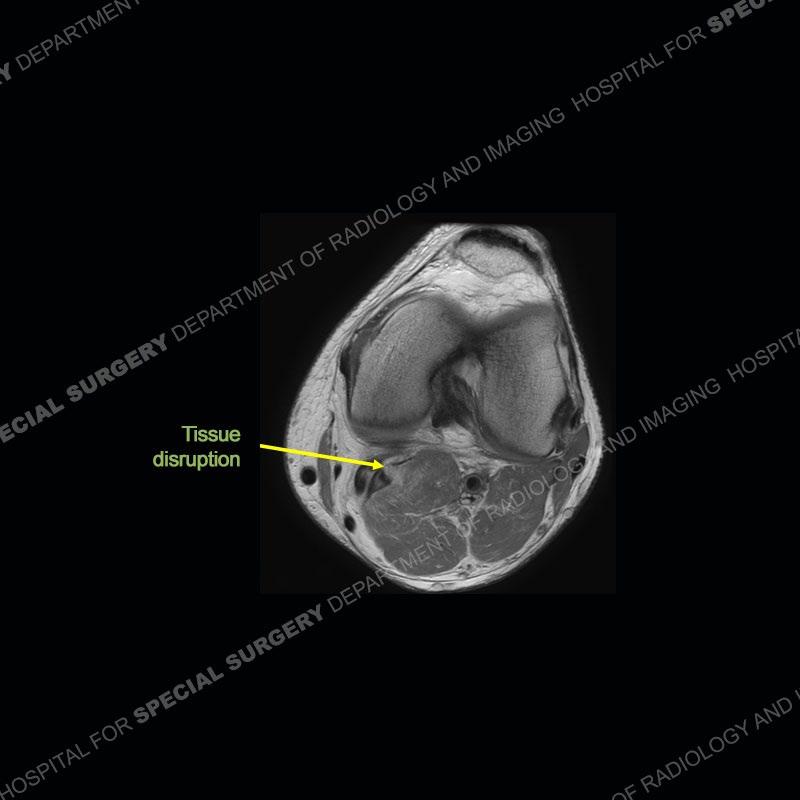

Findings

The radiographs show degenerative change of the medial compartment and a varus knee, but they are not germane to this case. No acute bony injury is present. The MRI shows edema of the posterior medial knee/soft tissue and a focal area of a partially disrupted low signal structure. The details are kept at a minimum in the findings of this case on purpose.

Diagnosis: Partial Disruption Medial Head Gastrocnemius (MHG)

The findings were kept purposefully vague as identifying the structures early on takes away a lot of the diagnosis. An uncommon entity and one of which we do not see a lot. Enthesopathic changes and tendinosis are seen as are distal MHG injuries, but proximal tears are rarely present. This case highlights a number of points. One, it almost always comes down to anatomy. Perhaps not a structure we normally spend too much time on, except save for diagnosing a Baker’s cyst, but knowing where this structure and all structures exist in all three planes is imperative. Second, when you think you are making a “call” or finding that you have never made before, step back and think is this just the abnormal presentation of a common pathology. That situation arises much more frequently. Third, if you look at it once, twice, and probably a third time and are confident in your odd or very rare diagnosis, stick to your guns. Especially, when it comes down to anatomic structures, the proof will be in the images.

Fourth, use all imaging planes and different pulse sequences to make your diagnosis. The edema highlighted in this case can be seen as the obscuration of fat on the PD images but is much easier to perceive as the high signal on the IR pulse sequences. The actual disruption of the MHG myotendinous junction is only able to be seen on the axial images. On the sagittal and coronal images, we get a sense something is wrong but hard to be exact. Lastly, when you look at a study and something just seems off (as I would say the sagittal and coronal images do with that dark band of tissue posteriorly), listen to yourself and go through the study slowly and meticulously. Most of the time you will find you were right, and something indeed is present.